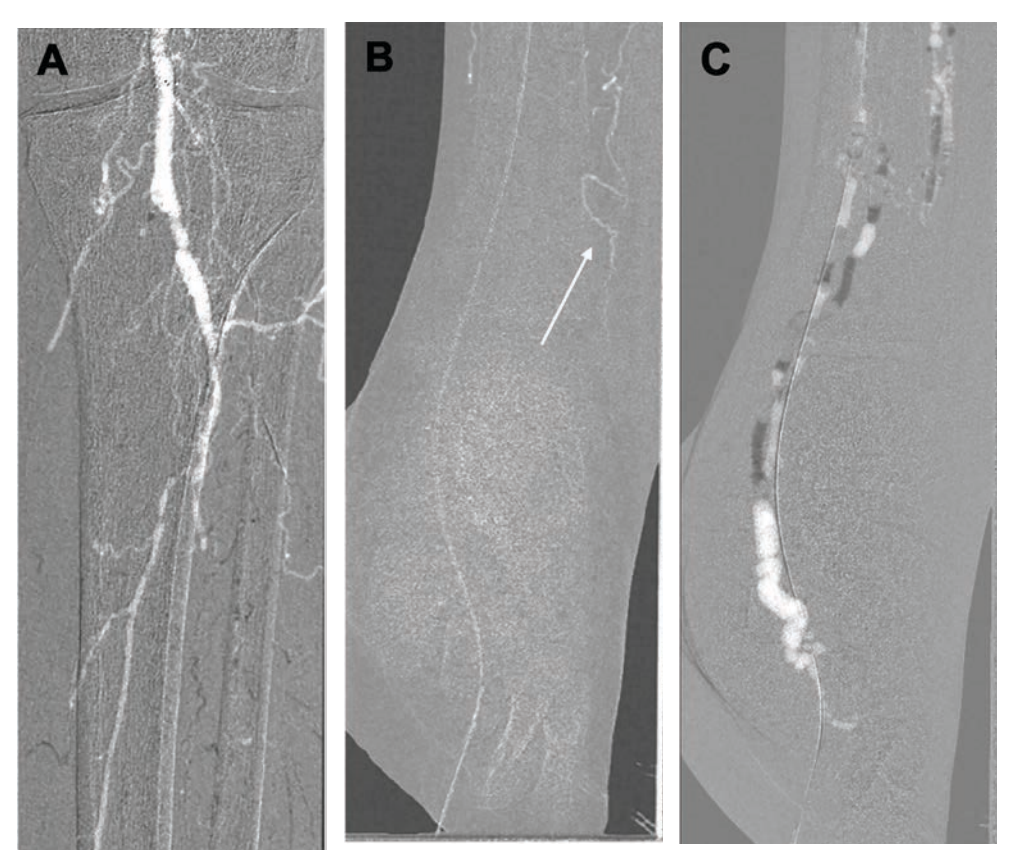

Eight years before the current presentation, the patient received a stent in the left popliteal artery (POP) followed by unsuccessful angioplasty of the tibioperoneal trunk (TPT). Subsequently, he underwent bypass from the left POP to the dorsalis pedis artery (DP) bypass using a cryopreserved vein to treat nonhealing foot wounds, but he ultimately required amputation of the left first-to-third digits. Three years later, he had a right below-knee amputation due to severe PAD. He presented now with left fifth-toe gangrene classified as Rutherford 6 with a Wound, Ischemia, foot Infection (WIfI) score of W2-I2-fI1, indicating a substantial risk of a major amputation. Prior foot x-ray demonstrated a medial arterial calcification (MAC) score of 4, which is a strong independent predictor of major amputation in patients with CLTI. He underwent a peripheral angiogram with 20-cc iodinated contrast at an outlying facility that revealed adequate inflow with a 75% stenotic lesion in the distal left POP (Figure 1). The POP-DP bypass and all 3 tibial vessels were chronically occluded, and he had an exuberant collateral formation in the foot.

Revascularization was done with ZCT using CO2 angiography, extravascular ultrasound (EVUS), and intravascular ultrasound (IVUS) to preserve his residual renal function given his post-renal transplant CKD. EVUS-guided antegrade left common femoral artery (CFA) access was obtained with a 6F Destination sheath (Terumo) as well as left lateral plantar vein (LPV) access with a Micropuncture catheter (Cook). Baseline angiographic images were obtained with CO2 angiography using the CO2mmander Elite device (AngioAdvancements), injecting 10cc for every selective angiogram (Figure 2). Notably, there was a short segment of patent proximal DP without visualization of the distal DP or the patent plantar arch of the foot to adequately perfuse the forefoot and heal a transmetatarsal amputation (TMA) (Figure 2b). IVUS-guided orbital atherectomy (Philips Eagle Eye Platinum ST) of the POP, TPT, and proximal posterior tibial artery (PTA) with a 1.5 Classic Diamondback catheter (Abbott) was performed. Thereafter, we performed IVUS-guided balloonangioplasty of the distal POP with a 5- x 80-mm Ultraverse balloon (BD) and balloon angioplasty of the TPT and PTA with a 4- x 120-mm Ultraverse balloon.

This case report describes a patient classified as no-option CLTI based on the following factors: This patient did not have any autologous venous conduits for surgical bypass. Foot X-ray revealed moderate-to-severe calcification with a MAC score of 4. He had W2-I2-fI1, indicative of a high amputation risk without revascularization. On CO2 contrast angiography, there was a segment of a patent proximal DP, but without evidence of distal branches or microvasculature that are needed to theoretically perfuse the forefoot and heal a TMA. Therefore, together with a history of prior failed revascularization attempts and severe small artery disease, the decision was made to defer another attempt at retrograde revascularization and instead pursue pDVA.